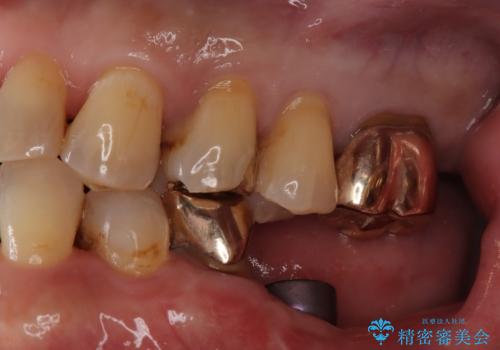

- 「フロスをしたら銀歯が取れた」を主訴に来院された患者様です。虫歯を除去した後、ゴールドインレーで治療を行いました。

隣の歯も虫歯になっており、その歯はCR(保険適応)で治療を行いました。

ゴールドインレーは天然歯と硬さが類似しているため、歯によく馴染み、対合歯(咬む相手の歯)が削れにくいのも特徴です。

左上4はゴールドインレー、左上5はCR(保険適応)で治療を行いました。